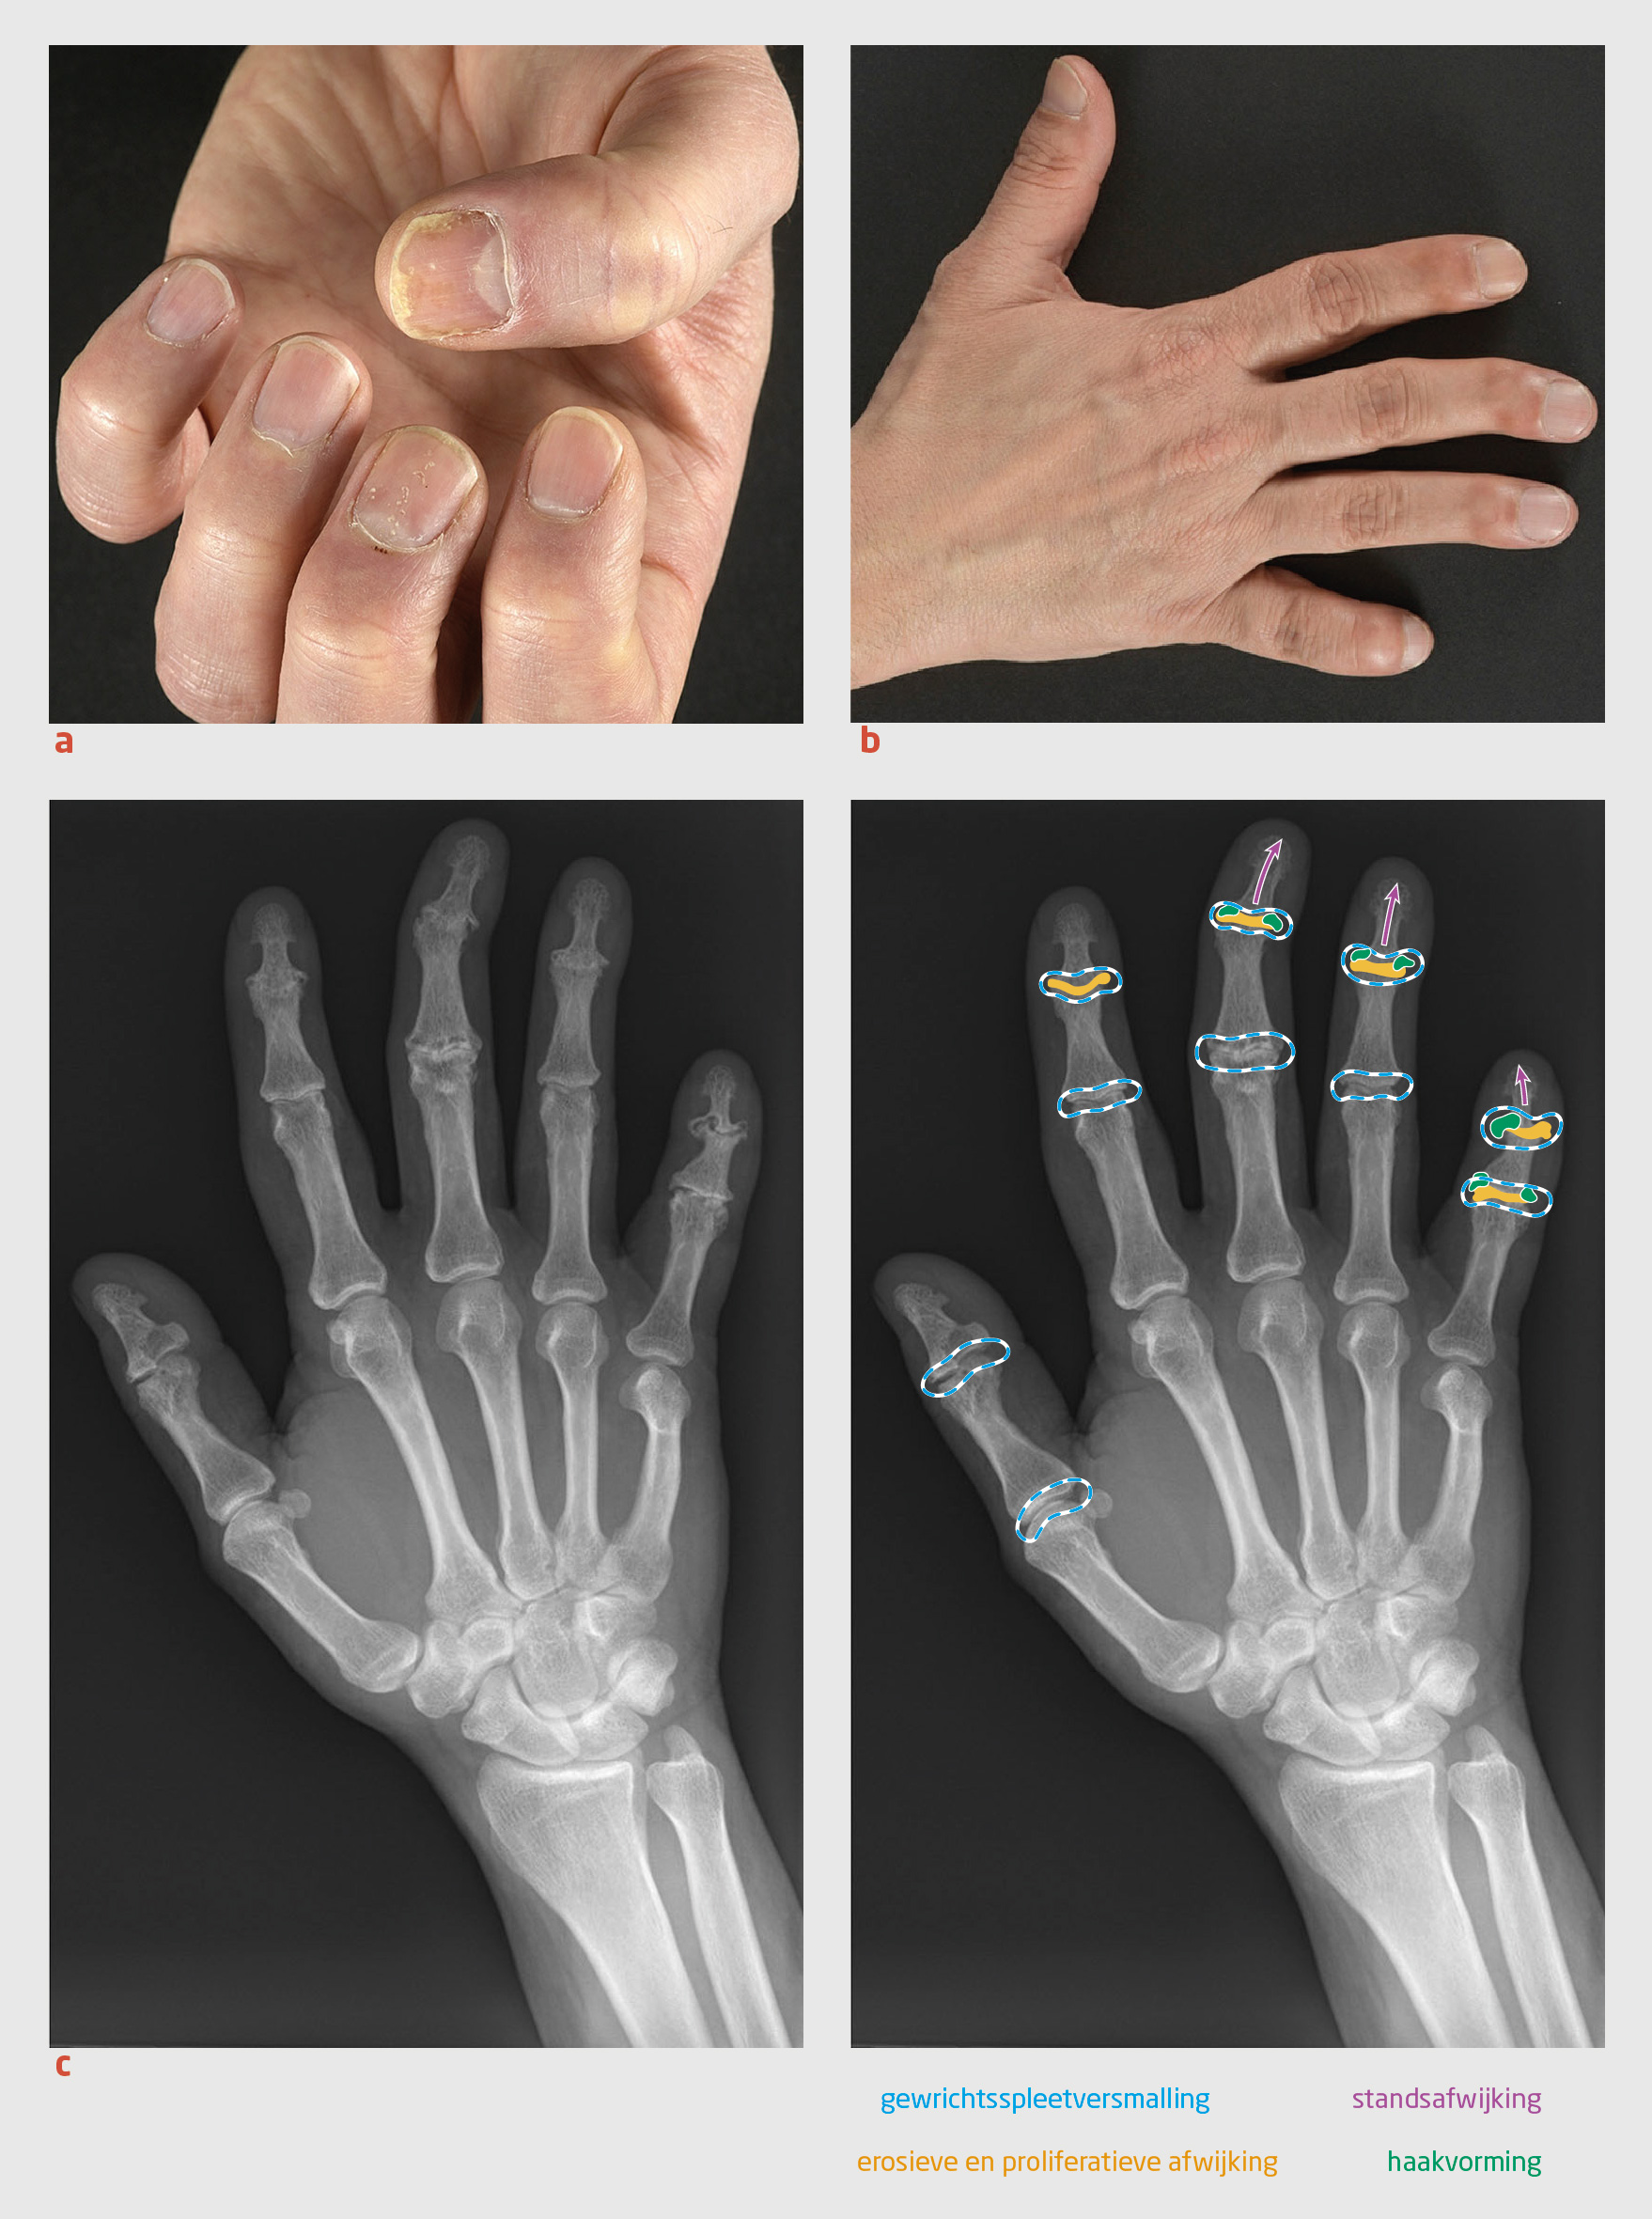

Figuur 2

Klinische manifestaties psoriasis en artritis psoriatica

Figuur 2 | Klinische manifestaties psoriasis en artritis psoriatica

(a) Subtiele nagelafwijkingen in de derde straal (putjes), eerste straal (distale loslating) en centraal (olievlekfenomeen). (b) Standsafwijkingen van de distale interfalangeale gewrichten met opvallende ulnaire deviatie van de derde en vierde straal, en verkorting van de vijfde straal. (c) Röntgenfoto van de hand met erosieve en proliferatieve veranderingen in de proximale en distale interfalangeale gewrichten, evenals gewrichtsspleetversmalling en haakvorming. Ook is er sprake van een standsafwijking van de distale interfalangeale gewrichten in de derde, vierde en vijfde straal.